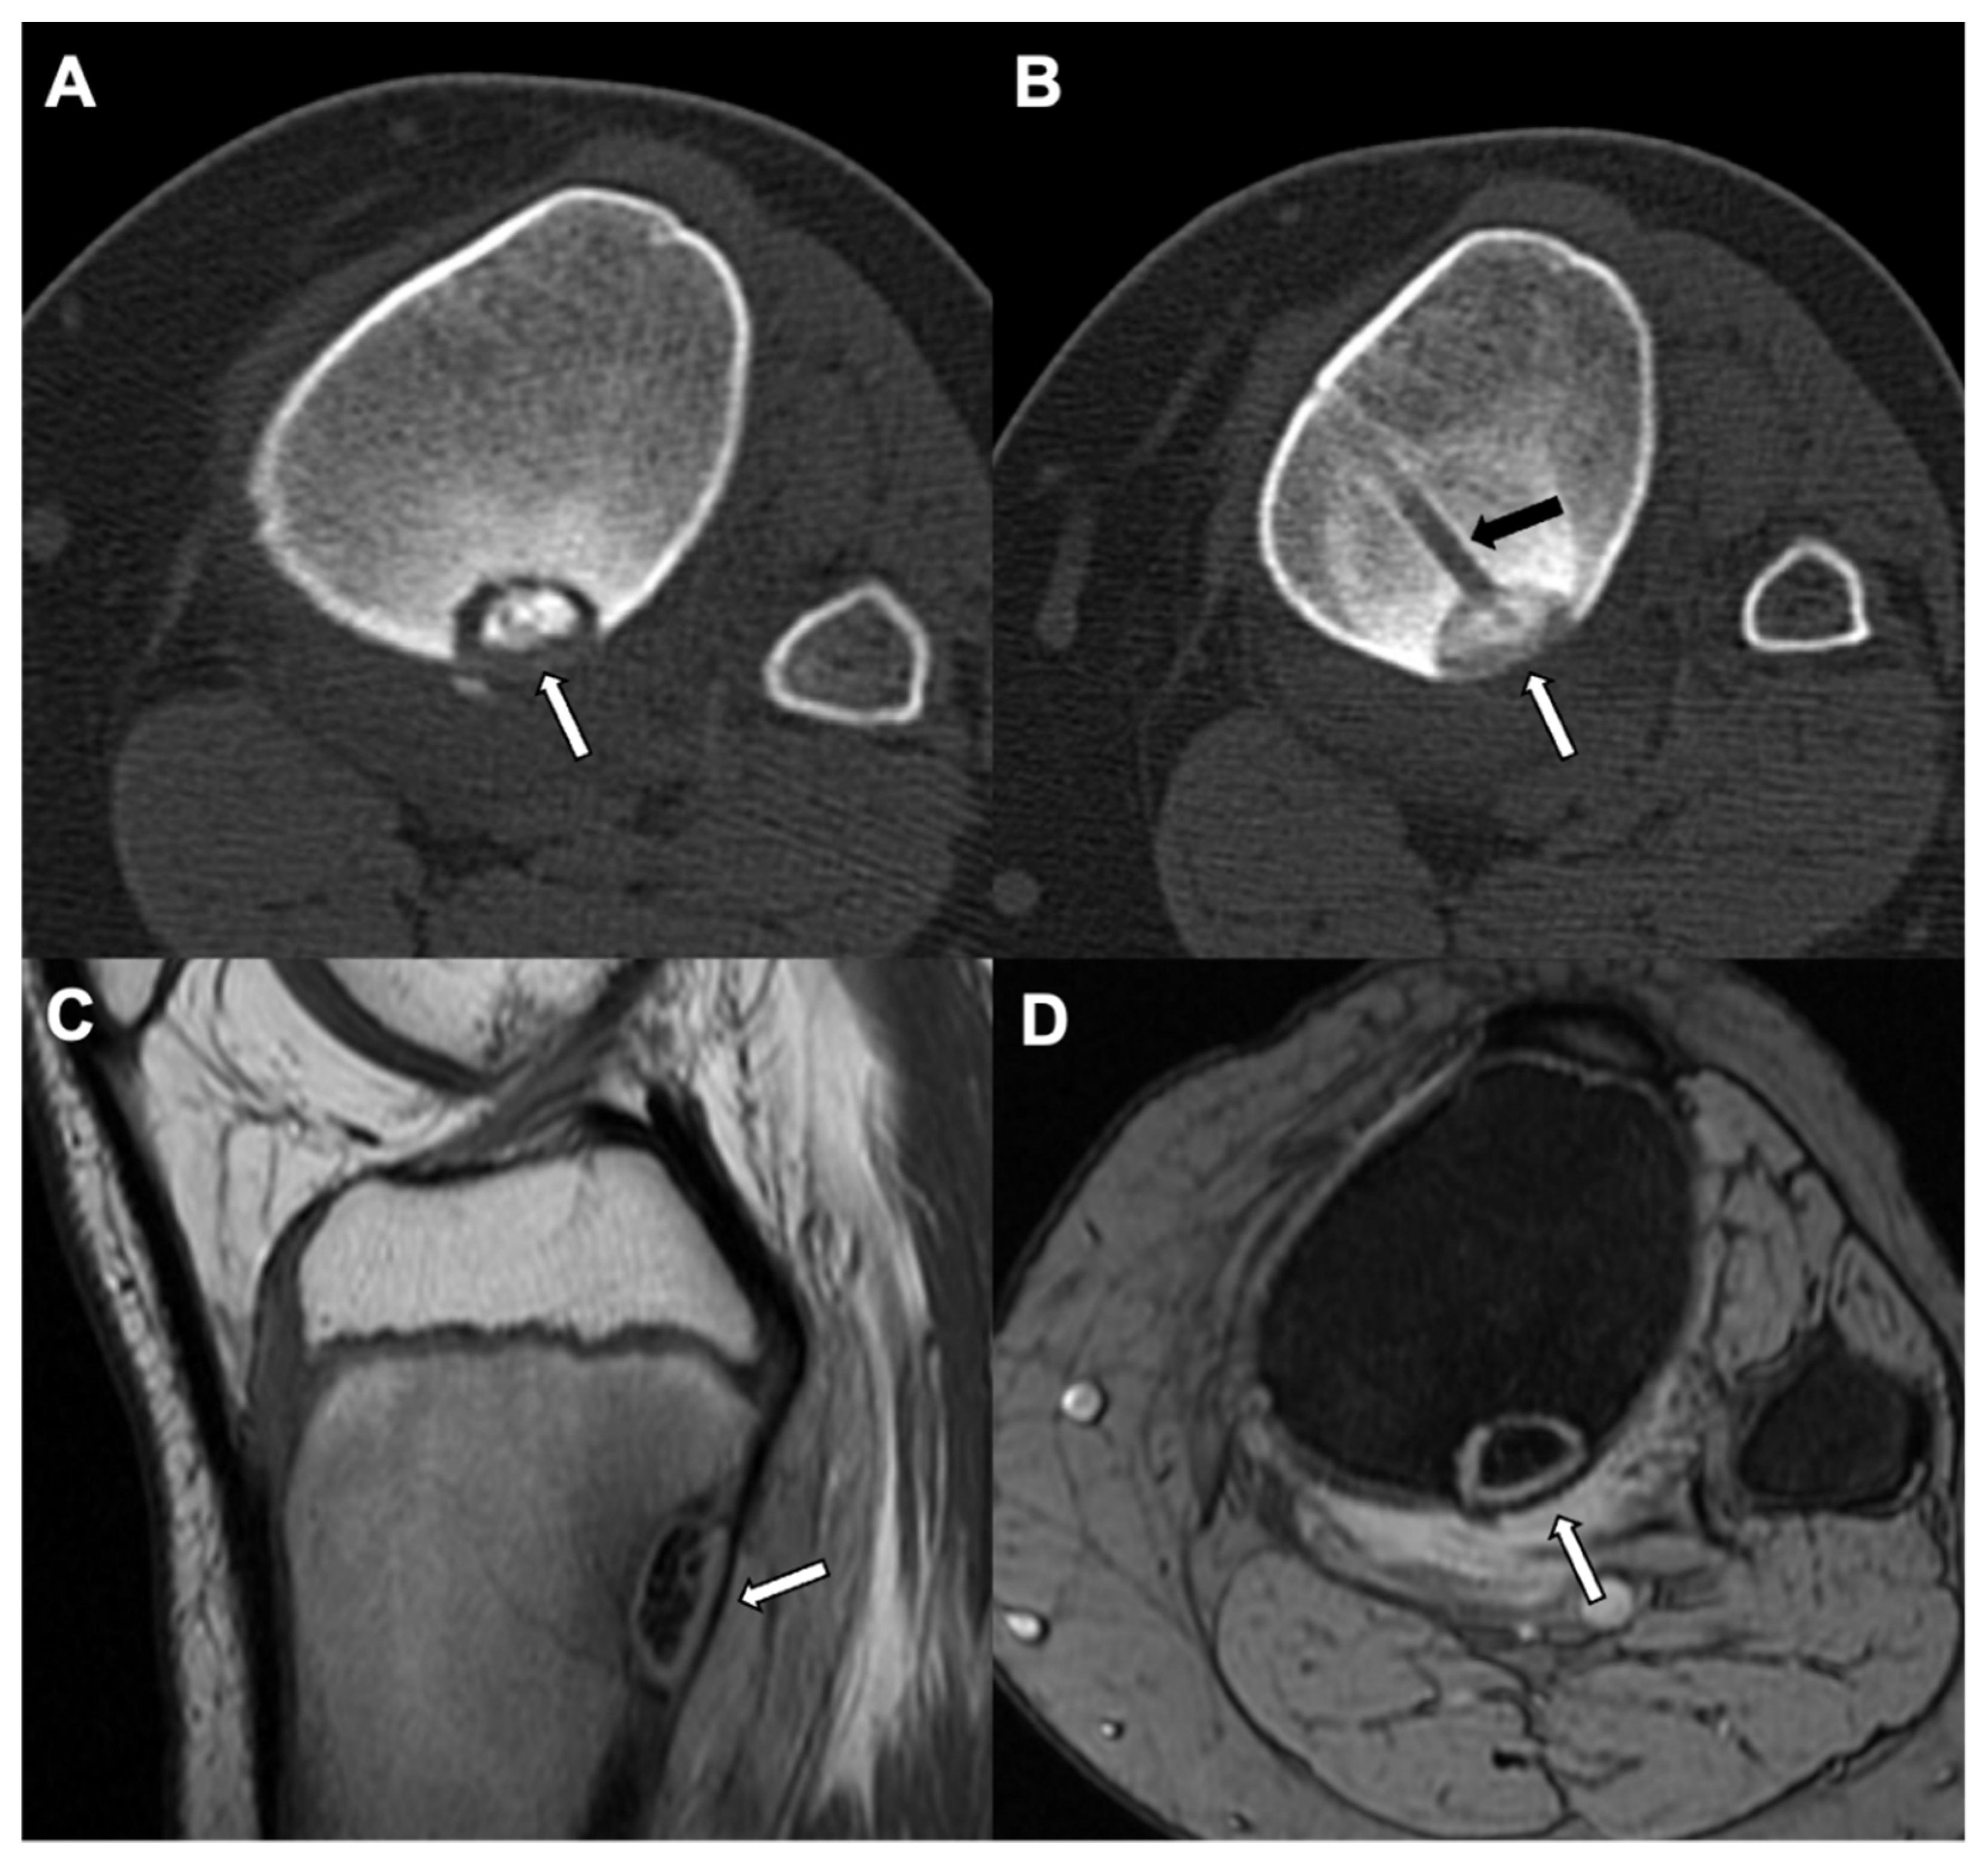

5. Osteoid Osteoma

- Iyer, R.S.; Chapman, T.; Chew, F.S. Pediatric Bone Imaging: Diagnostic Imaging of Osteoid Osteoma. Am. J. Roentgenol. 2012, 198, 1039–1052. [Google Scholar] [CrossRef]

- Liu, P.T.; Chivers, F.S.; Roberts, C.; Schultz, C.J.; Beauchamp, C.P. Imaging of Osteoid Osteoma with Dynamic Gadolinium-enhanced MR Imaging. Radiology 2003, 227, 691–700. [Google Scholar] [CrossRef]

| Radiographic/CT features | Juxtacortical, well-circumscribed homogenous sclerotic lesion | Homogenous intra-medullary sclerotic focus with spiculated margins | Small (less than 2 cm) cortical lucency with extensive surrounding sclerosis | Expansile large (more than 2 cm) lucent lesion with matrix mineralization |

| Treatment | None if asymptomatic; excision if complications related to mass effect | None | Percutaneous CT guided radiofrequency ablation | Surgery or percutaneous CT guided ablation |